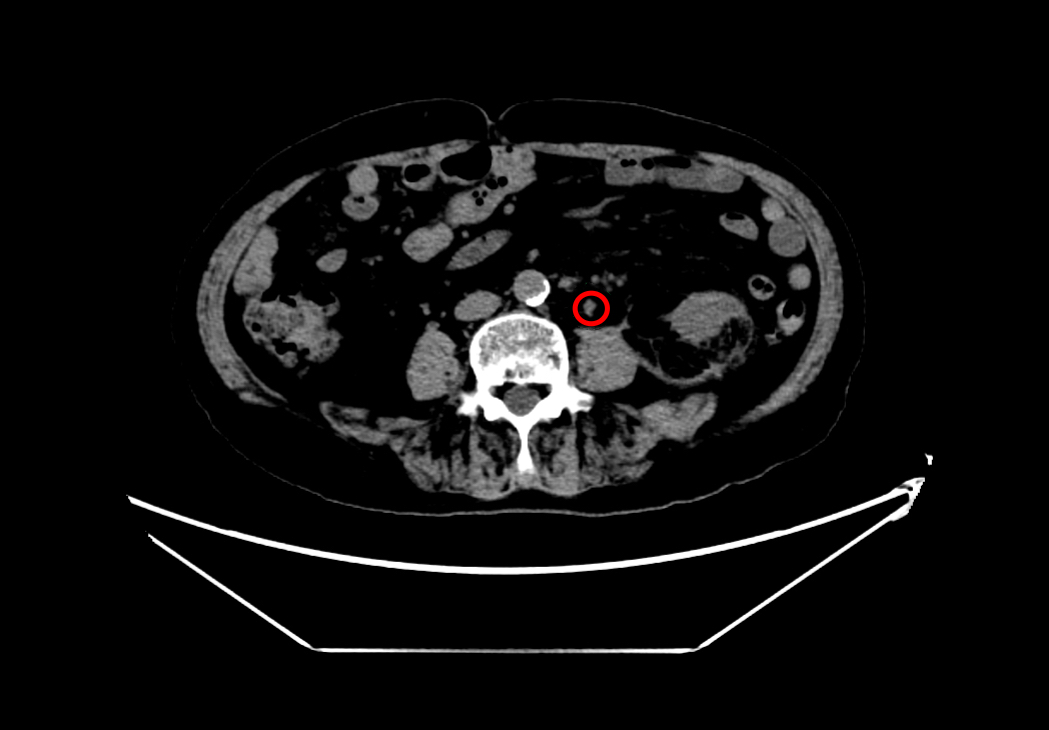

术后左侧输尿管

术后左肾

手术团队凭借丰富经验与精湛技术,精准建立经皮肾通道,顺利实施钬激光碎石取石及输尿管支架置入。术中患者出血少,生命体征平稳,手术圆满完成。